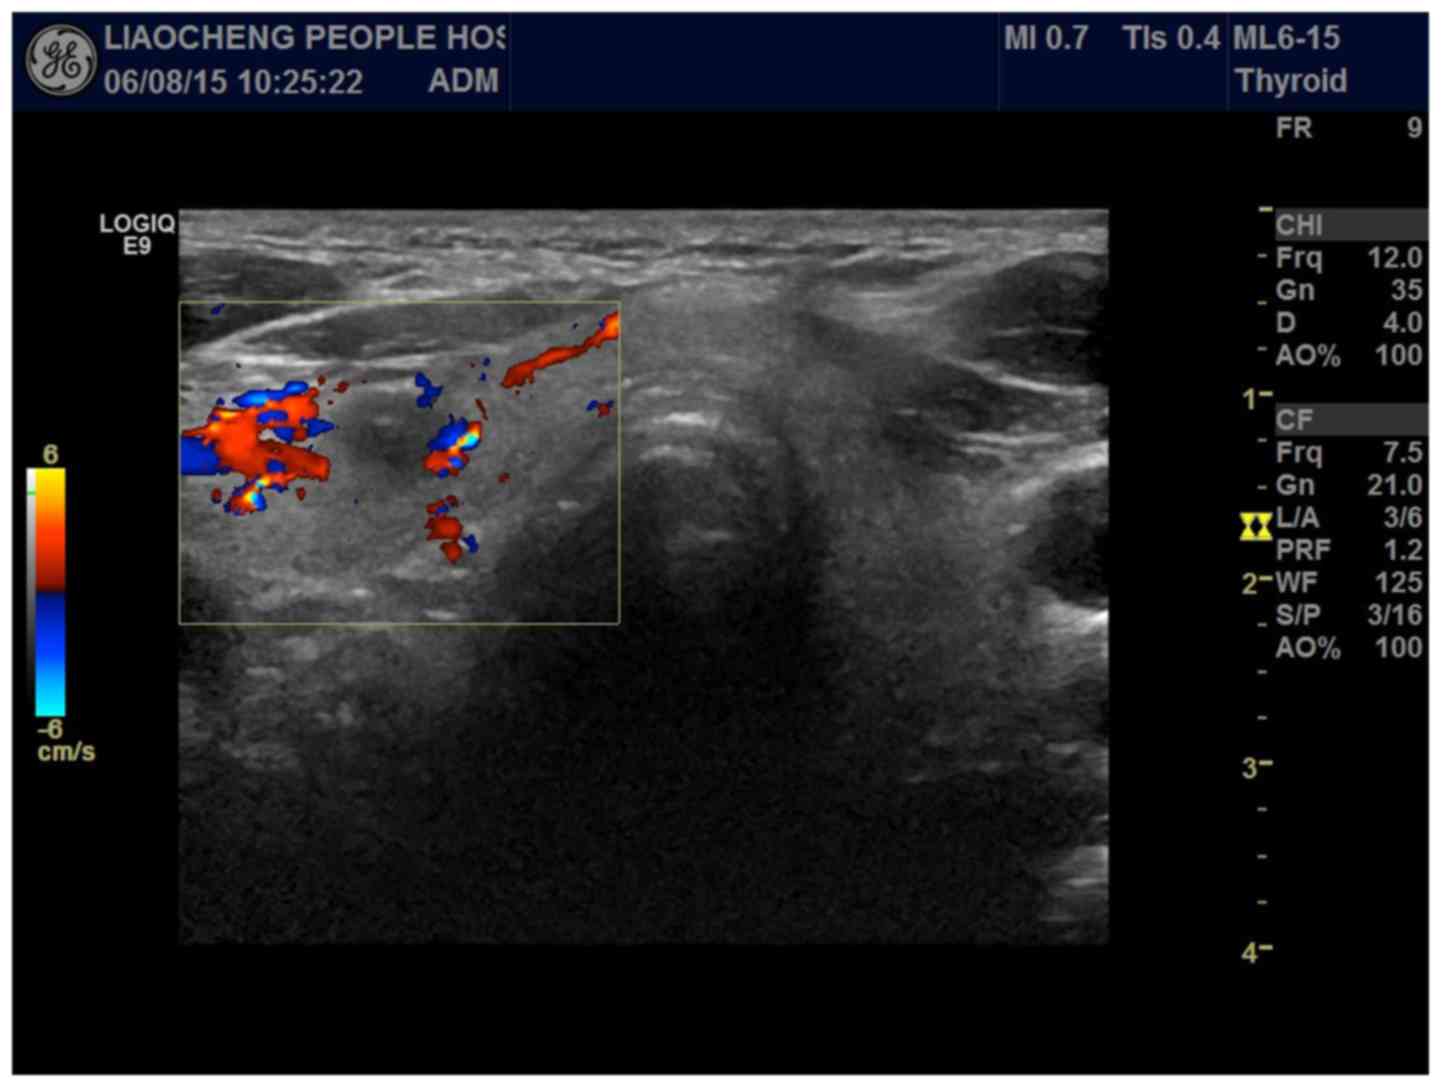

Thyroid Cancer Ultrasound Colors. Ultrasound images thyroid nodule color doppler echogramm 463 pin on thyroide a gallery of high resolution ultrasound color doppler 3d images thyroid related. Color on your thyroid ultrasound means that color doppler was applied and blood flow was detected. The staging system was developed by the american joint committee on cancer (ajcc) and is called the tnm system. Several reports have proposed that increased vascular flow on color doppler sonography may be associated with malignancy in thyroid nodules.

By definition, the flow towards the transducer is represented in red while the flow away from the transducer is represented in blue.

Cystic appearance, hyperechoic punctations / calcifications 2015 american thyroid association. The average speed is then converted to a specific color. The yellow arrow points to a nodule in the right side of the thyroid gland (the ultrasound pictures are a mirror image: The image of both the thyroid nodule and the surrounding thyroid tissue can present as red color affecting a large part of the thyroid gland beyond the nodule under investigation. The staging system was developed by the american joint committee on cancer (ajcc) and is called the tnm system.

Increased color doppler flow is suspicious. Cystic appearance, hyperechoic punctations / calcifications 2015 american thyroid association. A thyroid ultrasound is a safe, painless procedure that uses sound waves to examine the thyroid gland. It accounts for the majority (~70%) of all thyroid neoplasms and 85% of all thyroid cancers 2,4. The main symptom of thyroid cancer is a lump or swelling in the front of the neck just.

Hypervascularity is a typical finding in people with underlying autoimmune thyroiditis (hashimoto�s or graves disease). Thyroid disorder grayscale ultrasound color doppler key features; The risk of cancer increased with the size of. The image of both the thyroid nodule and the surrounding thyroid tissue can present as red color affecting a large part of the thyroid gland beyond the nodule under investigation. However, a cystic lymph node in the bottom half of the neck is most commonly a diagnosis of papillary thyroid cancer.

A thyroid lobe has the shape of the rotation ellipsoid. The risk of cancer increased with the size of. The purpose of this study was to determine whether the vascularity of a thyroid nodule can aid in the. The average speed is then converted to a specific color. Color on your thyroid ultrasound means that color doppler was applied and blood flow was detected.